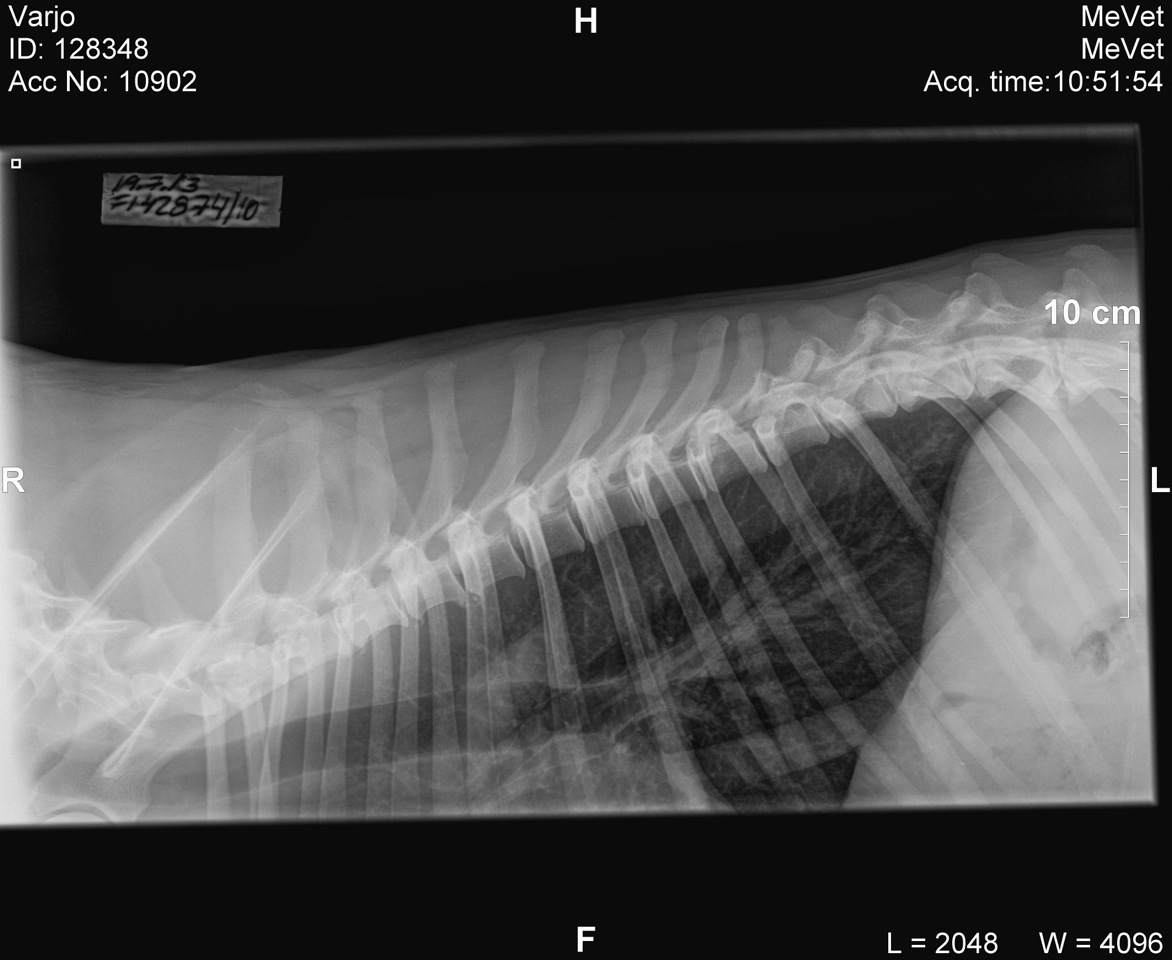

Qeisari luustokuvattiin 4.8.11.

Kuvatuissa nivelissä ja selkärangassa ei havaittu muutoksia.

Hännän ensimm.nikama luutunut yhteen ristiluun kanssa. Ell Ventelän mukaan muutos ei tule aiheuttamaan koiralle oireita.

Pyysin myös pieneläinsairauksien erikoiseläinlääkäri Anu Lappalaiselta lausunnon kuvista ja muutoksen perinnöllisyydestä

: "Koirilla on tosiaan ristiluu muodostunut 4 nikamasta. Se on koirilla varsin yleistä. Muista roduista

en tiedä, mutta mäyräkoirilla sitä esiintyy noin 8 %:lla koirista. Terveyden kannalta sillä ei ole merkitystä, mutta onhan

se varmasti perinnöllistä. Minulla ei ole tietoa siitä, miten se liittyy muihin, vakavampiin nikamamuutoksiin, ehkä ei mitenkään.

Mielestäni tämä muutos ei ole este jalostukselle, mutta ihannetapauksessa tietysti toisella osapuolella voisi olla normaalisti

luutunut ristiluu ja normaali lanne-ristiluuliitos."